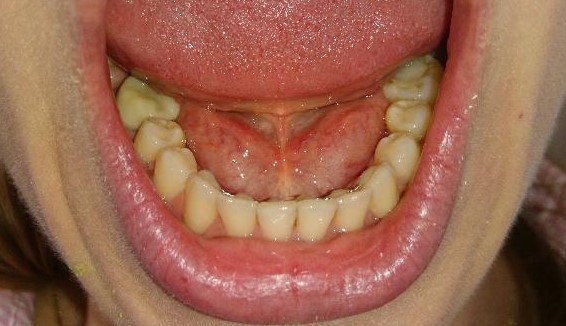

Pacient, 26 ani. Caz nonextracționist, Expander Maxilar + aparate ortodontice fixe bimaxilare.